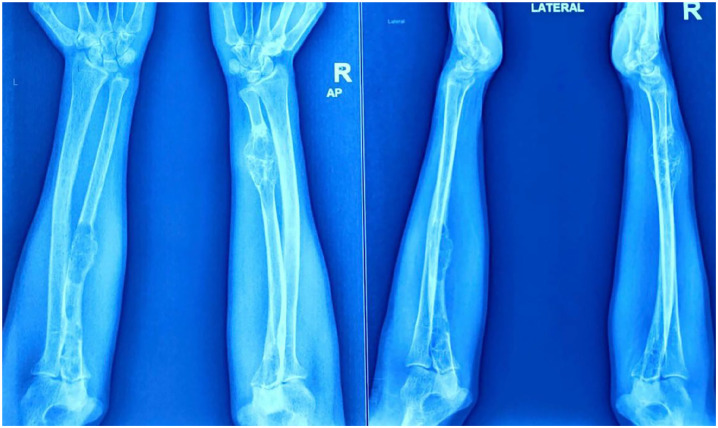

Brown tumors, though rare, are significant manifestations of hyperparathyroidism, often presenting with multifocal osteolytic lesions and occasionally leading to pathological fractures. This case report details the presentation and management of a 38-year-old male with multifocal brown tumors, including a right tibial fracture, and provides a comprehensive literature review. The patient exhibited multiple osteolytic lesions in the legs, thighs, and forearms, alongside elevated serum calcium and parathyroid hormone (PTH) levels. Management included conservative fracture treatment, surgical resection of the parathyroid adenoma, and postoperative rehabilitation. Follow-up revealed significant tibial fracture healing and reduction in the size of osteolytic lesions. This report underscores the importance of timely diagnosis and comprehensive management to prevent complications and improve outcomes in patients with multifocal brown tumors.